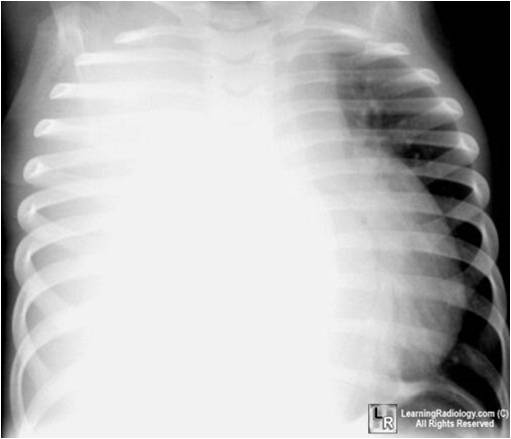

weekly clinical round for undergraduate from 8 to 11 AM during which interpretation of CHEST X rays was done for all cases of cardiothoracic surgery, gived by 2 staf member for 3 months